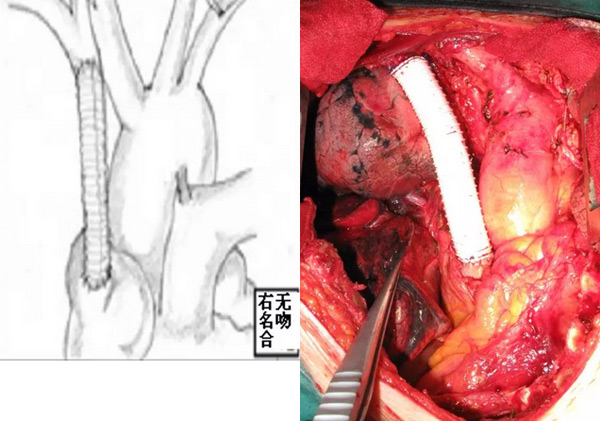

山东省立医院东院胸外科采用一侧无名静脉与右心房吻合通血,再完成肿瘤及受累上腔静脉的切除,再完成另一侧无名静脉与上腔静脉近心端的吻合,或仅吻合一侧无名静脉与左心房。这样整个手术过程不存在上腔静脉阻断的问题,从而避免了该类手术最大的风险,即脑缺血。

(3)人造血管与右(或左)无名静脉及右心耳吻合、左(或右)无名静脉结扎,上腔静脉无阻断